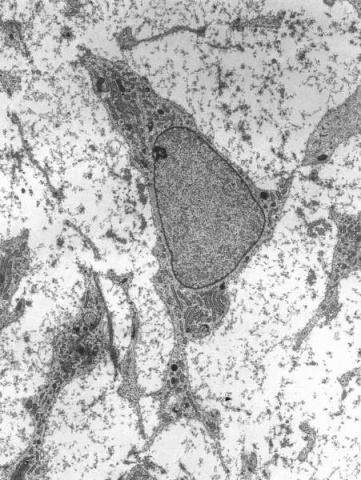

Célula humana (en tonos de azul) infectada por partículas víricas del coronavirus SARS-COV-2 (en color naranja). (Imagen: U.S. National Institute of Allergy and Infectious Diseases / NIH)